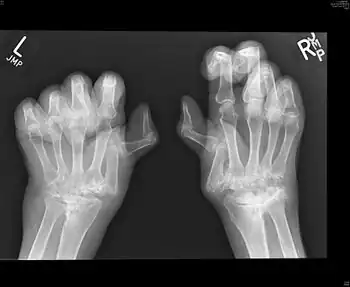

Palindromic rheumatism (PR) is a syndrome characterised by recurrent, self-resolving inflammatory attacks in and around the joints, consists of arthritis or periarticular soft tissue inflammation.[1] The course is often acute onset, with sudden and rapidly developing attacks or flares. There is pain, redness, swelling, and disability of one or multiple joints. The interval between recurrent palindromic attacks and the length of an attack is extremely variable from few hours to days. Attacks may become more frequent with time but there is no joint damage after attacks. It is thought to be an autoimmune disease, possibly an abortive form of rheumatoid arthritis.

Palindromic rheumatism is a syndrome presented with inflammatory para-arthritis (soft tissue rheumatism) and inflammatory arthritis both of which cause sudden inflammation in one or several joints or soft tissue around joints. The flares usually present with mono- or oligo-articular involvement,[4] which have onset over hours and last a few hours to a few days, and then go away completely. However episodes of recurrence form a pattern, with symptom-free periods between attacks lasting for weeks to months. The most commonly involved joints were knees, metacarpophalangeals and proximal interphalangeals.[4] Constitutionally, there may or may not be a fever, and swelling of the joints. The soft tissues are involved with swelling of the periarticular tissues, especially heel pads and finger pads. Nodules may be found in the subcutaneous tissues.[1] The frequency of attacks may be variable over the course but there is no joint damage after attacks.[1]